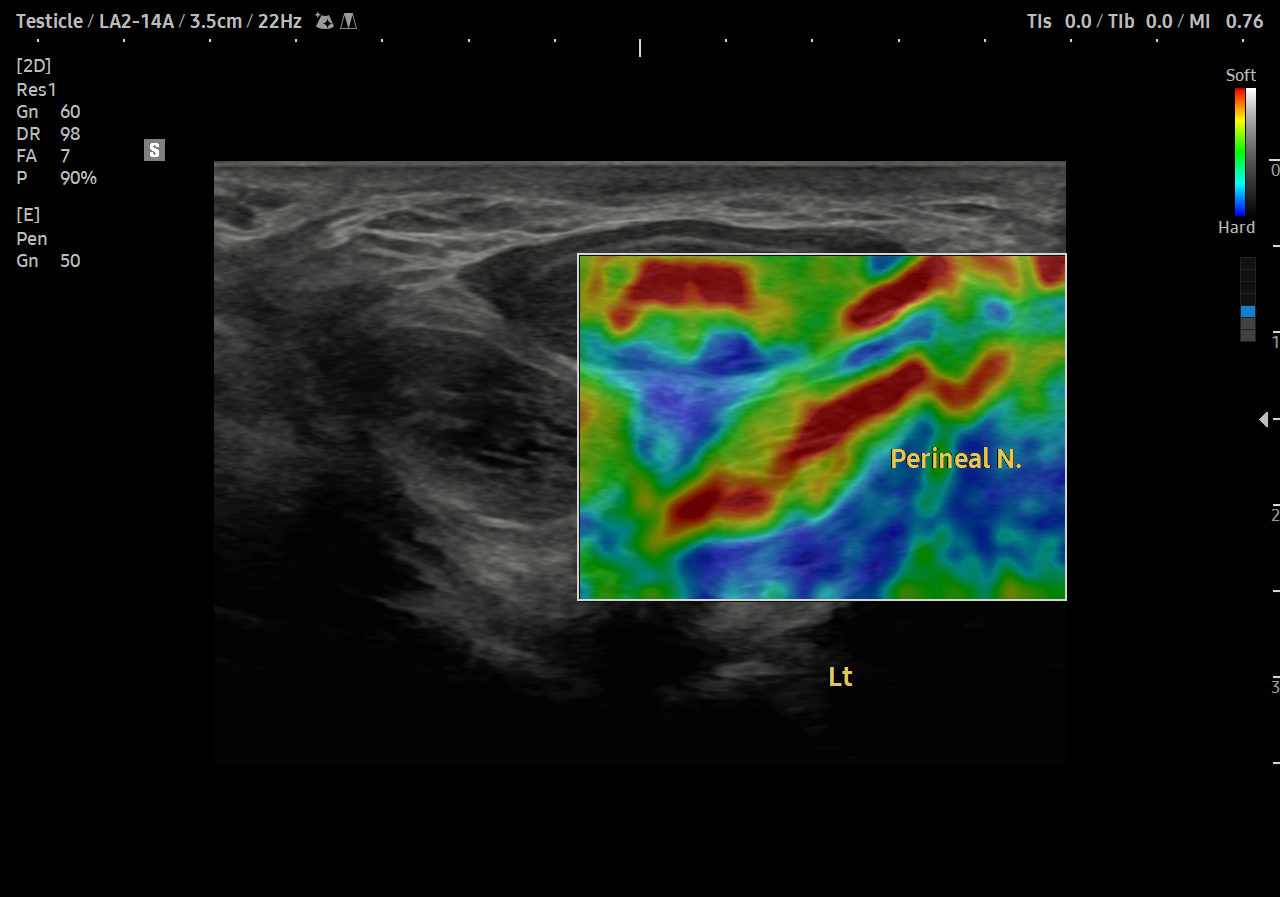

통증 부위를 살펴볼까요?

회음부의 통증과 치골부위 통증이 심했습니다.